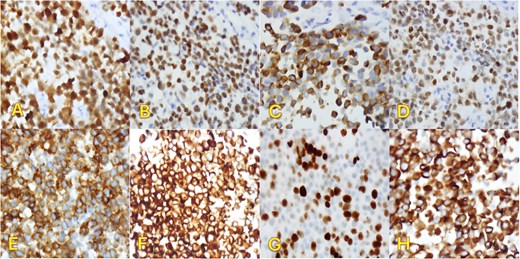

An fluorodeoxyglucose positron emission tomography-computed tomography (PET-CT) scan showed highly suspicious metabolically active malignancy and associated metastasis involving the cluster of right upper lobe pulmonary nodules, right-sided pleural effusion/thickening, right-sided pleural nodularity extending along the fissure, multiple mediastinal lymph nodes and an avid lymph node within the post-thyroidectomy bed (Fig. 1c). As the patient was not a surgical candidate, the interventional radiologist performed an ultrasound-guided core biopsy, and pleurodesis with doxycycline was done through the pigtail catheter. The patient was discharged a week later with a stable X-ray and on Lovenox medication. His serum LDH level was elevated by 58 points, and Calcitonin was in the normal range. H&E staining revealed malignant cells with variable size, nuclear irregularity, and eosinophilic cytoplasm, indicating cancerous tissue within the pleura (Fig. 2). However, the exact primary origin of these malignant cells remained undetermined. Extensive immunostaining was performed to identify the source of the malignancy. Tumor cells were strongly positive for S100, SOX10, Melan-A, MITF, CD99, BCL2, WT, and Ki 67 at 40%–50%, confirming a diagnosis of metastatic melanoma (Fig. 3).

Right pleural biopsy: (A) sheets of metastatic cells H&E (×40), (B) round to oval malignant cells with eosinophilic cytoplasm, no melanin pigmentation was detected H&E (×400).

Immunohistochemical staining (×400). Pleural biopsy was strongly positive for (A) S100, (B) SOX10, (C) Melan-a, (D) MITF, (E) CD99, (F) BCL2, (G) Ki67, and (H) WT1.